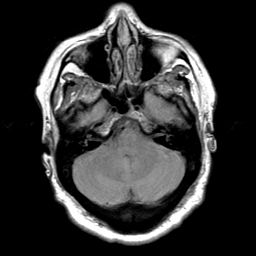

Cerebral hemorrhage, MR Study mr-pd -- Slice #6

[Home][Help][Clinical] Slice 6